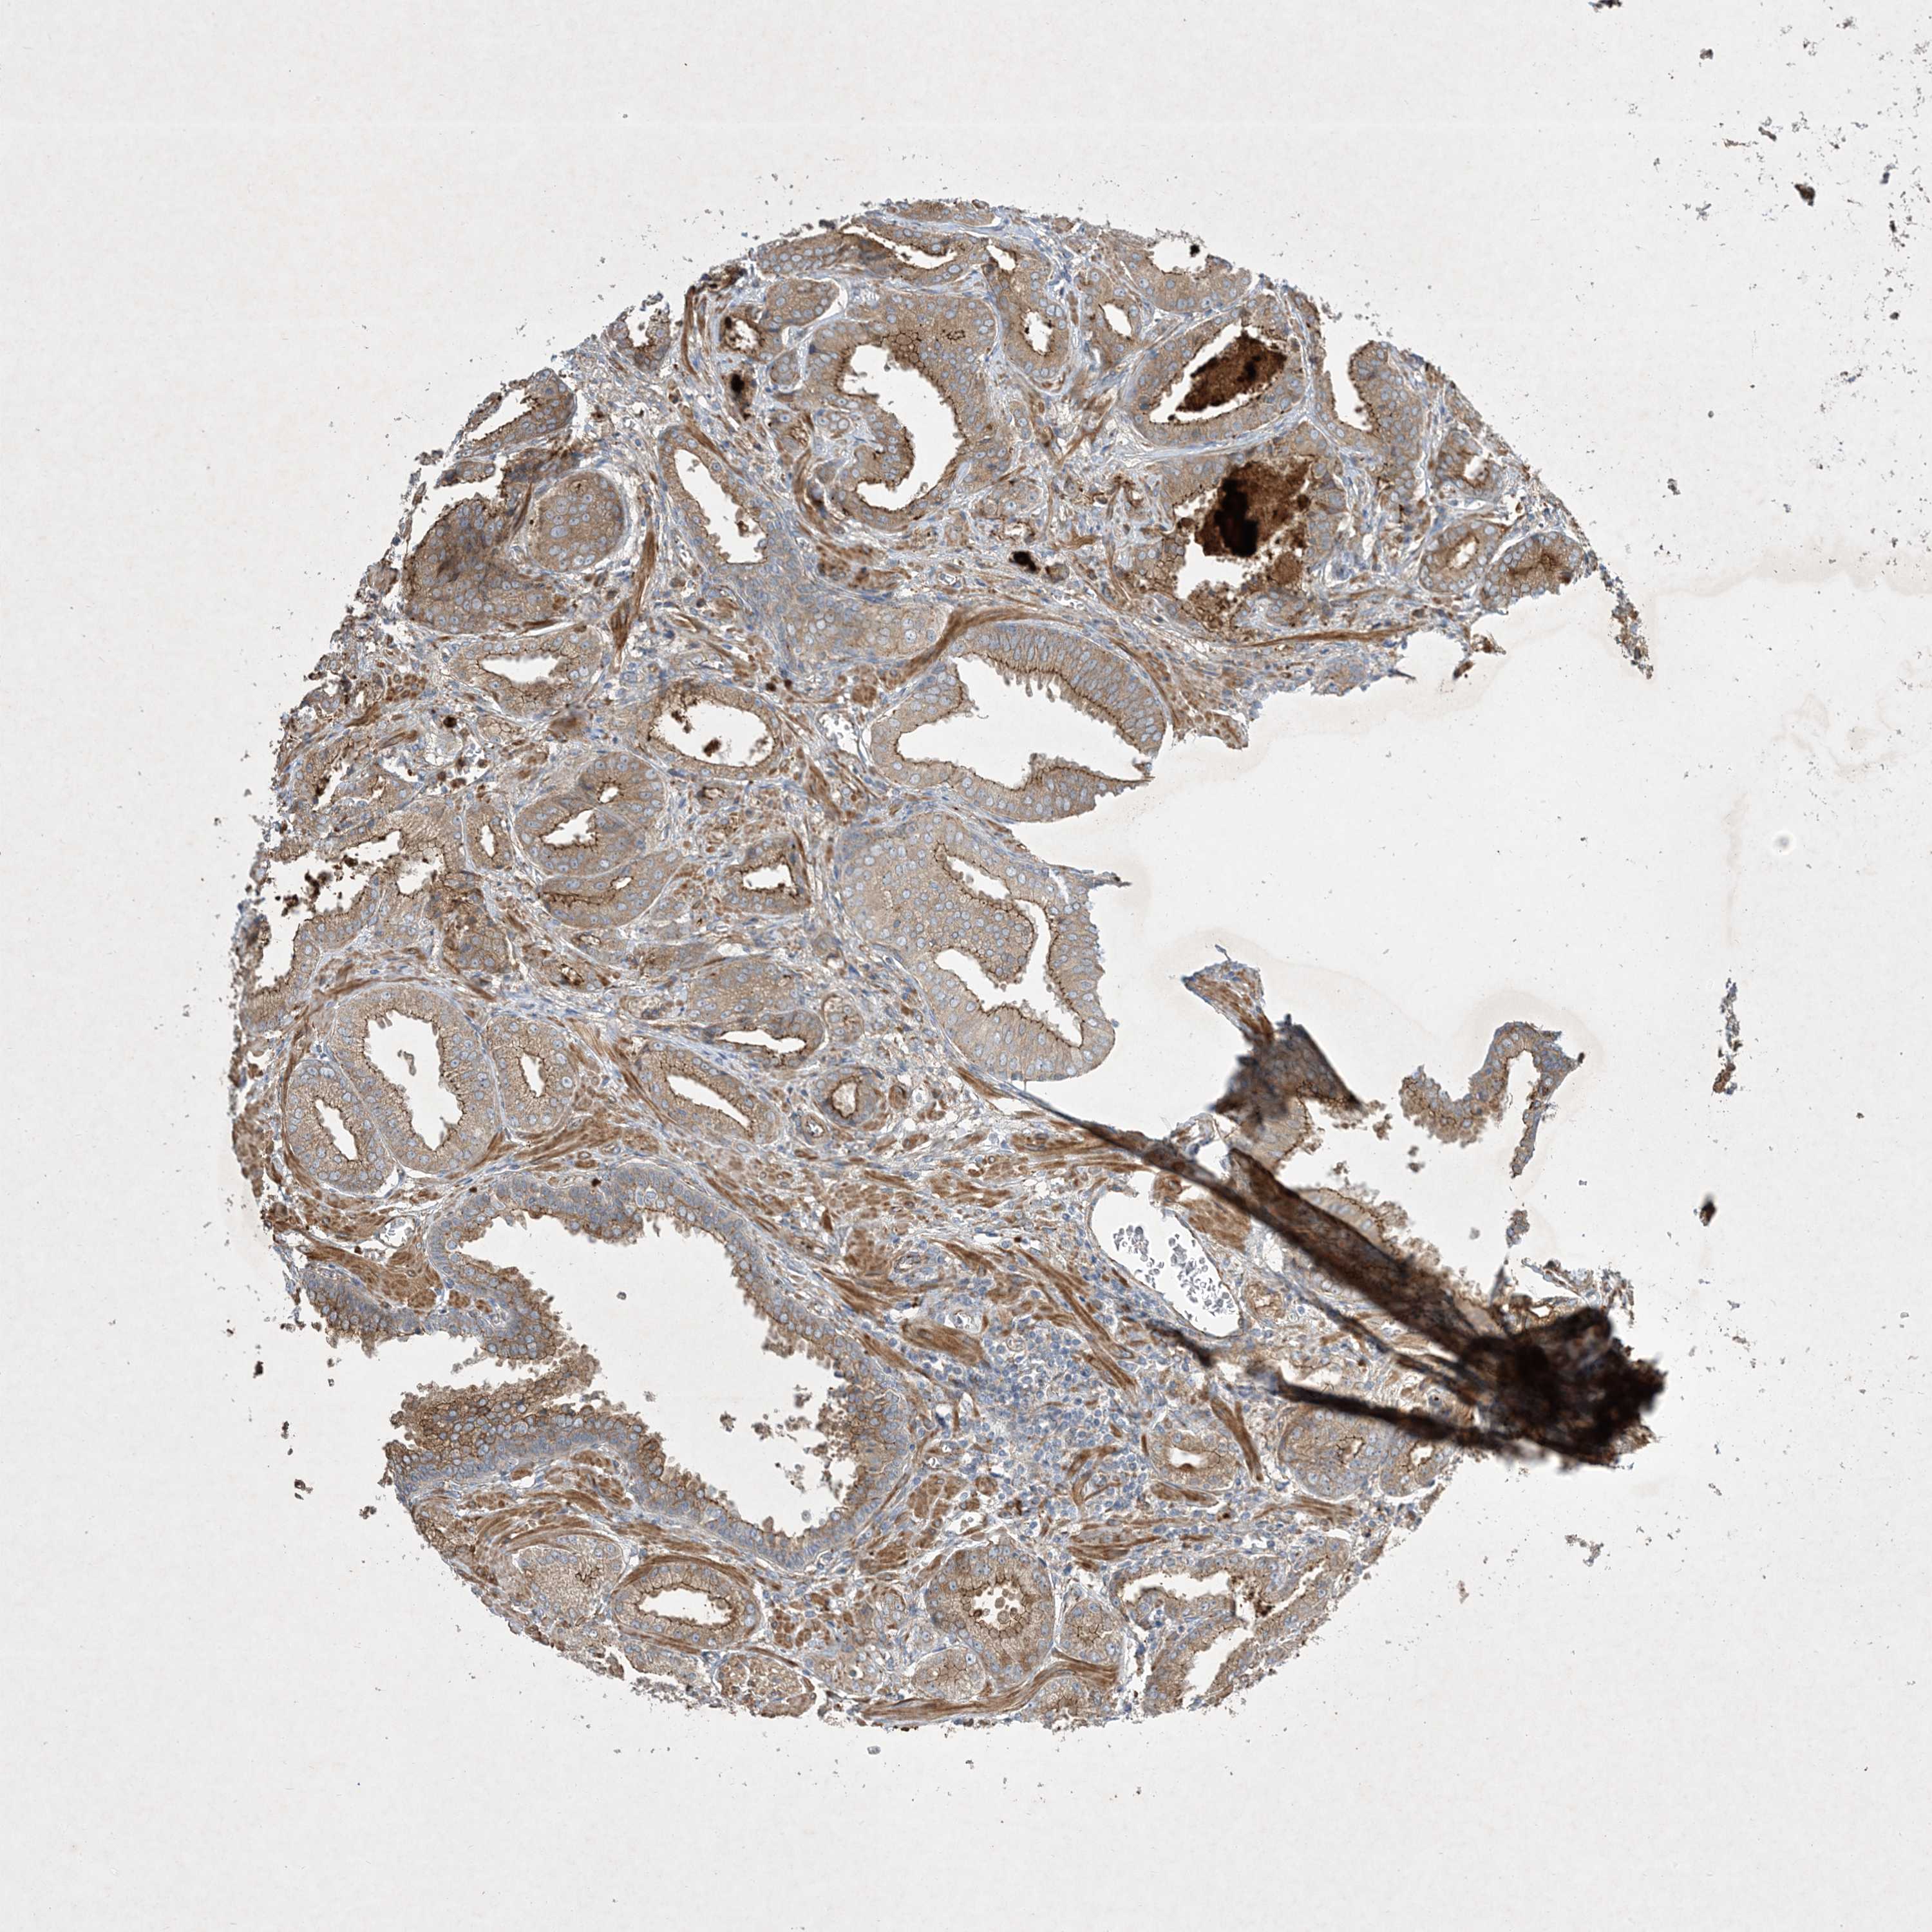

PROSTATE CANCER - Protein expressioni

A mouse-over function shows sample information and annotation data. Click on an image to view it in a full screen mode. Samples can be filtered based on level of antibody staining by selecting one or several of the following categories: high, medium, low and not detected. The assay and annotation is described here.

Note that samples used for immunohistochemistry by the Human Protein Atlas do not correspond to samples in the TCGA dataset.

Antibody stainingi

Antibody staining in the annotated cell types in the current human tissue is reported as not detected, low, medium, or high, based on conventional immunohistochemistry profiling in selected tissues. This score is based on the combination of the staining intensity and fraction of stained cells.

Each image is clickable and will lead to virtual microscopy that enables deeper exploration of all samples and also displays staining intensity scores, fraction scores and subcellular localization as well as patient and tissue information for each sample.

Antibody HPA035599

Staining

High

Medium

Low

Not detected

Intensity

Strong

Moderate

Weak

Negative

Quantity

>75%

75%-25%

<25%

None

Location

Nuclear

Cytoplasmic/membranous

Cytoplasmic/membranous,nuclear

Adenocarcinoma, High grade

Adenocarcinoma, Low grade